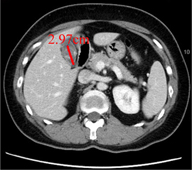

膽結石是膽囊內結晶化的硬塊,可能導致右上腹劇痛、噁心、嘔吐等症狀。根據病情,無症狀的膽結石患者可以選擇觀察,但對於反覆疼痛或高風險的患者,如結石直徑超過3公分或伴隨糖尿病,建議手術治療。

近3公分膽結石併腹痛